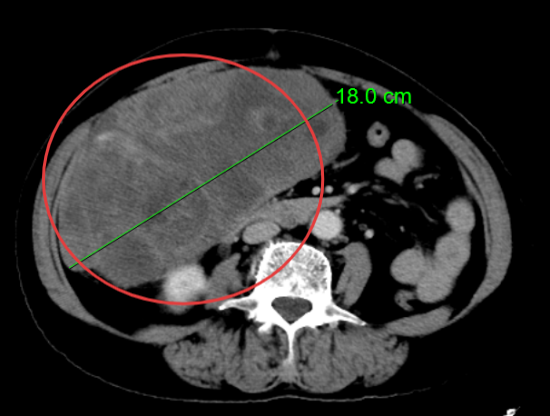

患者杨阿姨,因右下腹胀痛持续一月入院,经过详细的腹部CT检查,结果显示其腹腔内存在一个巨大占位性病变,最大层面大小竟达到了惊人的18cm×10cm×14cm,肿瘤性质及来源尚不明确。面对如此庞大的肿瘤,手术难度可想而知。然而,杨阿姨的身体状况更为复杂。术前检查发现,她全心扩大,心脏彩超显示三尖瓣大量反流,肺动脉高压、二尖瓣大量反流,肺动脉瓣中量反流,并伴有心动过缓。这些心脏问题无疑为手术增添了巨大的风险。面对这样心功能极差的患者,任何微小的失误都可能导致不可挽回的后果。

CT报告结果